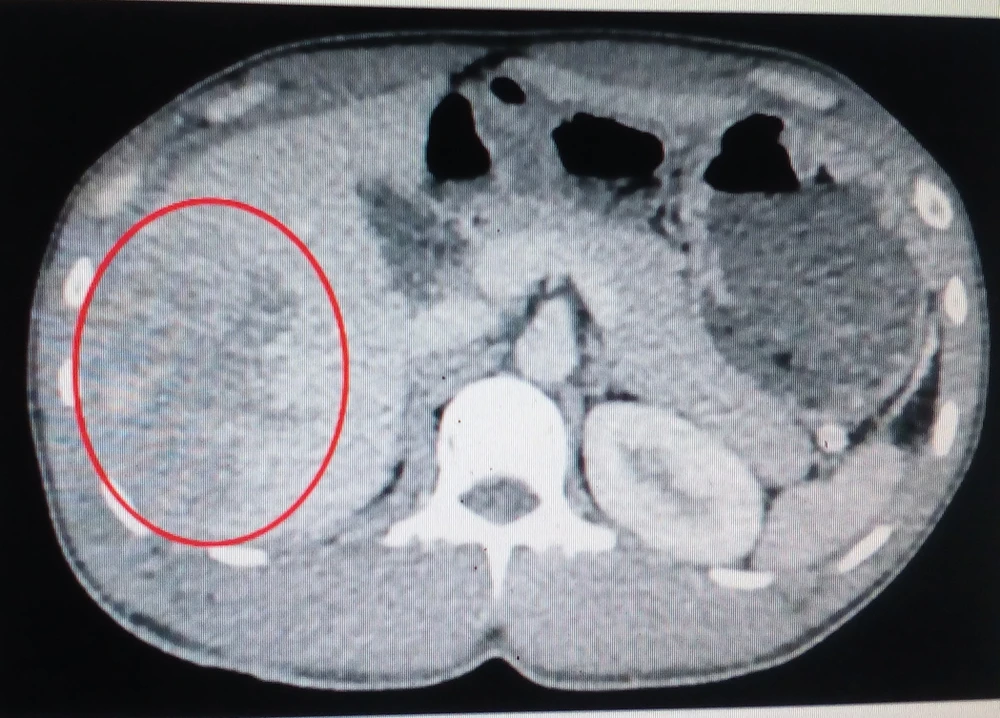

Kết quả chụp CT 160 lát cho thấy gan của anh T. bị vỡ nhiều đường  phức tạp. Ảnh: LÊ PHỤNG

Khi mổ cấp cứu mở ổ bụng, bác sĩ thấy nhiều máu đỏ tươi, gan vỡ nhiều đường phức tạp và chảy nhiều máu. Các bác sĩ khâu cầm máu gan, rửa sạch ổ bụng, đặt dẫn lưu douglas... Hiện sức khỏe anh T. hồi phục rất tốt.